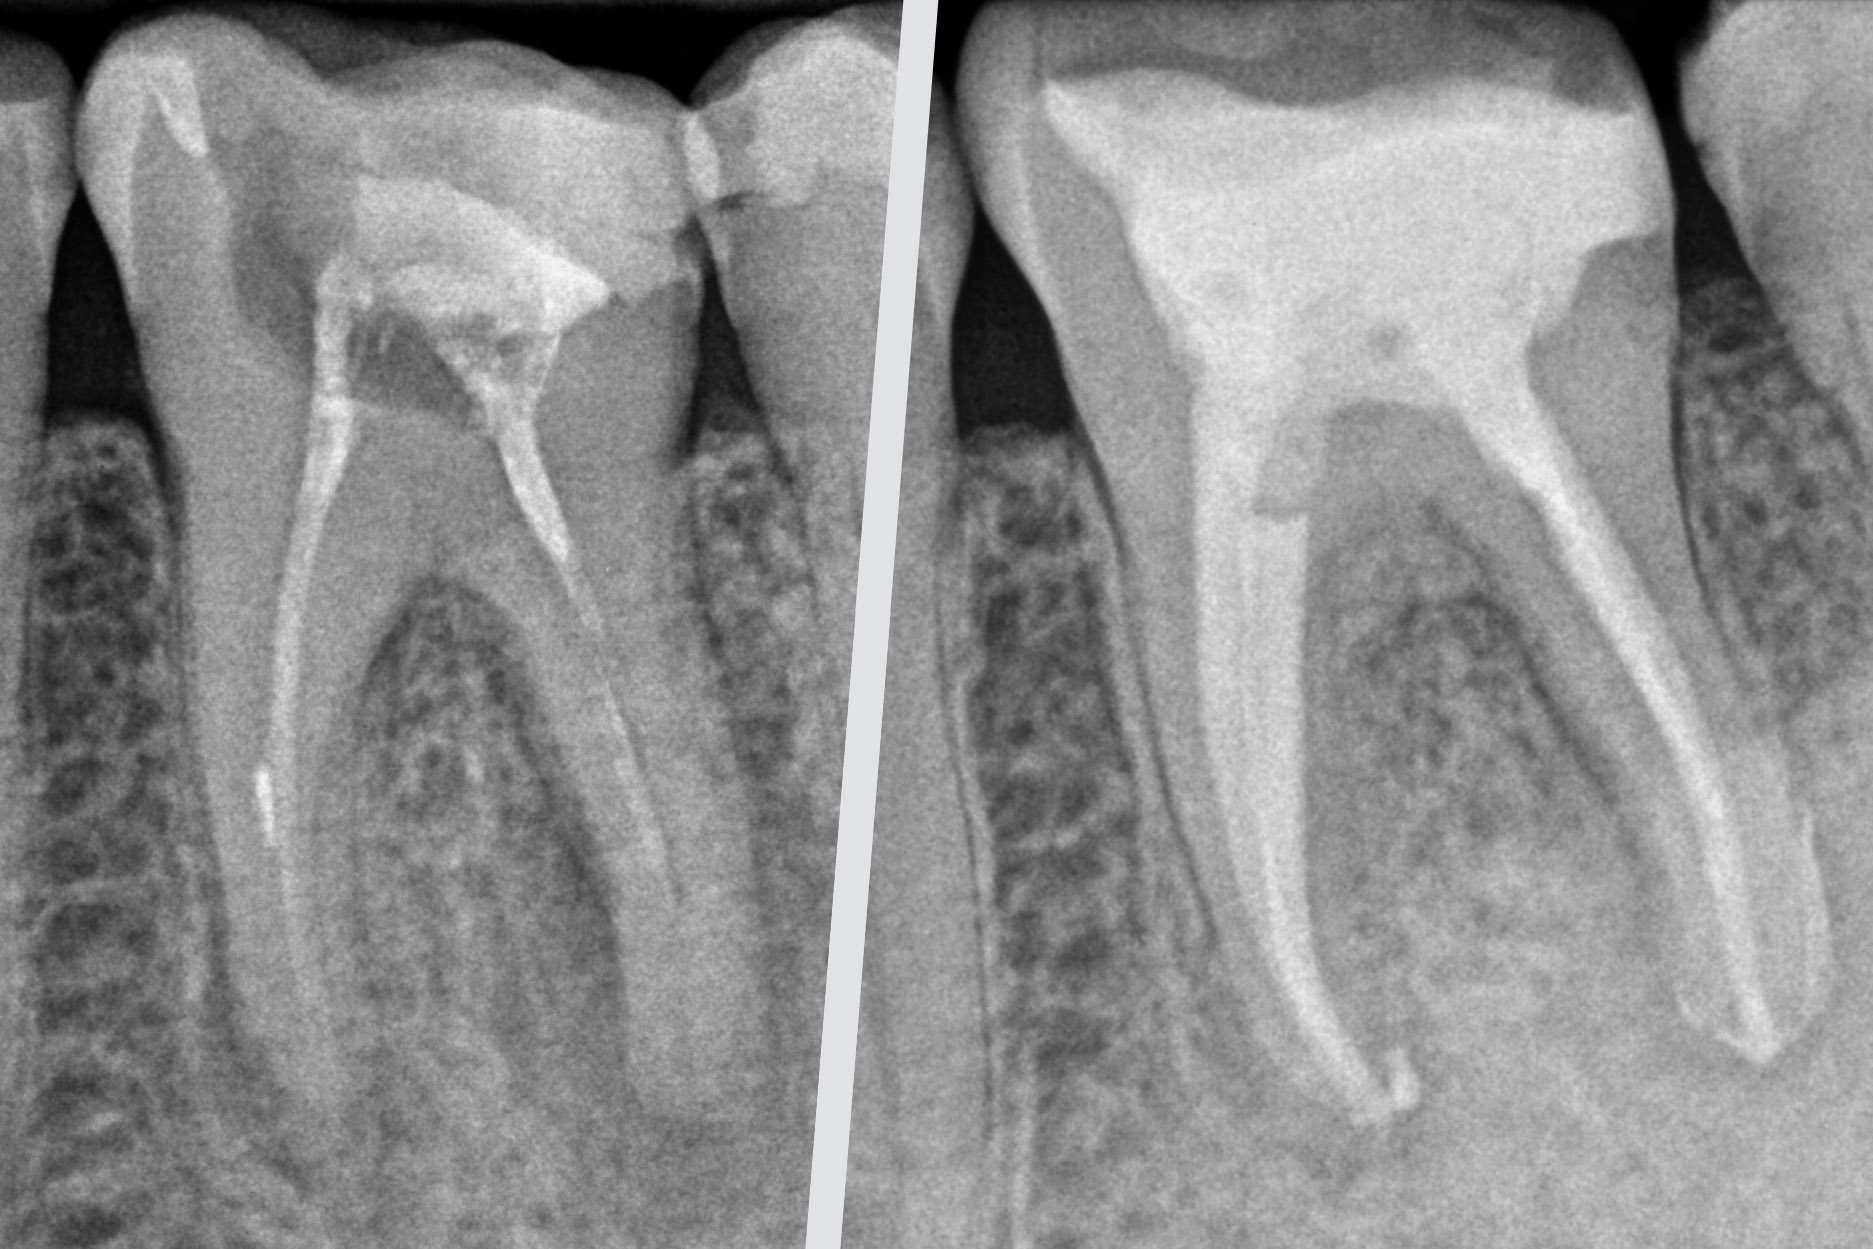

Endodoncie se zabývá ošetřením kořenových kanálků. K infekci zubní dřeně dochází obvykle v případě neléčeného zubního kazu nebo úrazu. Cílem je odstranění infikované dřenědostatečná chemická dezinfekce kořenových kanálků tak, aby je bylo možné zaplnit kořenovou výplní a zub po rekonstrukci mohl dále zůstat ve funkci.

Reendodontické ošetření je opakované ošetření kořenových kanálků v případě, že primární ošetření nebylo úspěšné. Důvodem mohou být nedostatečně zaplněné kanálky, infekce, zalomený kořenový nástroj, perforace, nenalezený kořenový kanálek apod. Cílem je odstranění původní kořenové výplně infekce tak, aby bylo možné zub opětovně zaplnit a zachoval se funkční zub bez zánětu. Někdy je nutné zákrok doplnit periapikální chirurgií (resekce kořenového hrotu), kterou provádíme ve spolupráci s našimi chirurgy.